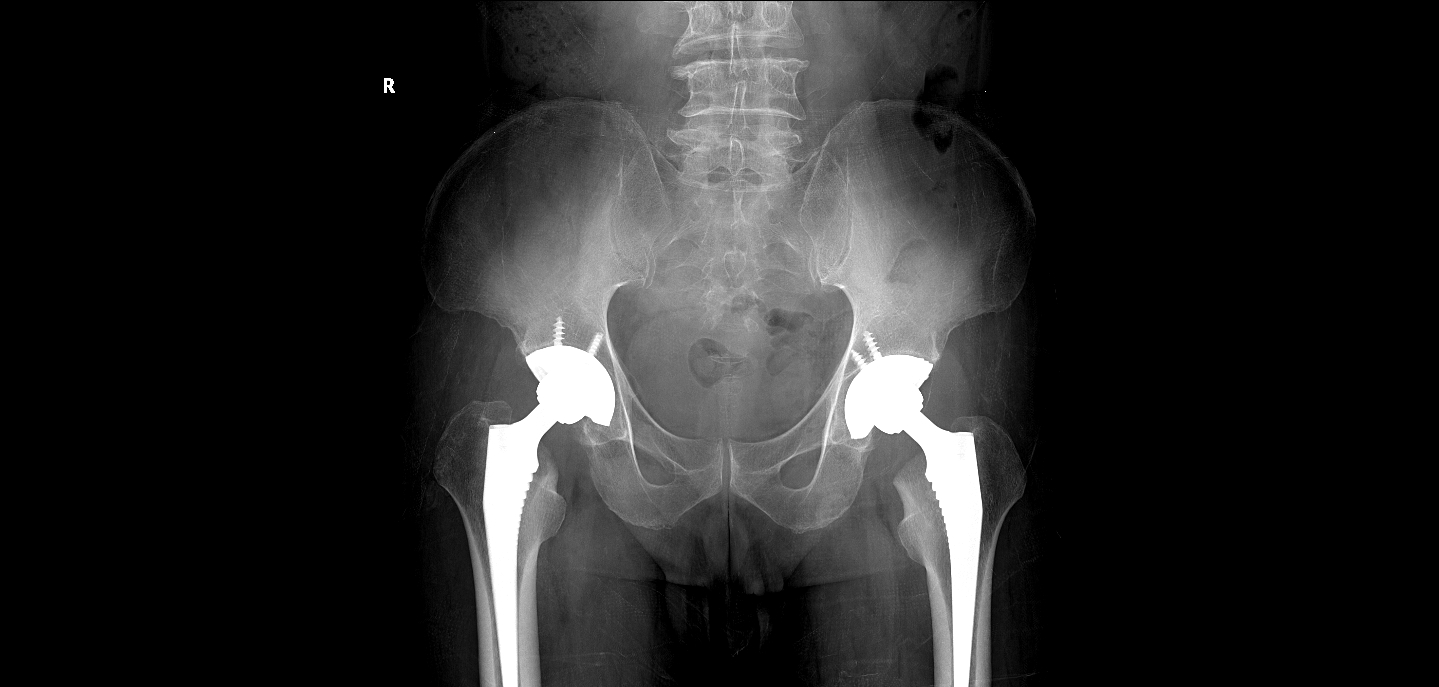

患者文伯,男,65岁,因双侧髋关节疼痛3年余于2017-04-11步行入病房。患者于3年前无明显诱因出现双髋关节疼痛,无其他部位放射痛,当时未重视,未行任何处理。2017年3月到宜恩县民族医院就诊,行双髋关节MR平扫提示:双侧股骨头坏死(未见报告),予活血化瘀及外用药物治疗后症状未见明显缓解,病情逐渐加剧,现已无法下地行走。查体:双侧髋关节周围压痛(+)、叩击痛(+),双髋活动受限,四肢肌力肌张力正常,肢体血运、感觉正常。入院后行双髋关节CT平扫提示:双侧股骨头无菌性坏死。于2017-4-14送手术室在全麻下行“双侧髋关节置换术”,术程顺利,术后患者恢复可,可自行下地行走,双髋关节疼痛已缓解。

术后